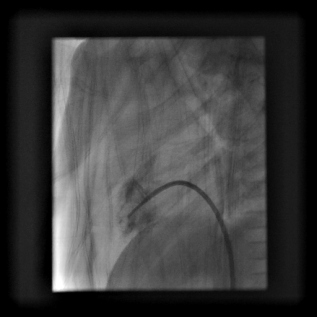

心导管检查:介入治疗

√ 堵闭治疗:缺损,异常管道

√ 扩张治疗及支架植入: 瓣膜和血管狭窄

√ 增加房间交通:复杂畸形